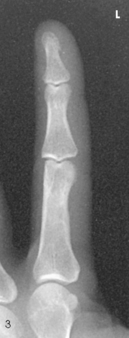

Position of part: When radiographing individual digits (except the first), take the following steps:

• Place the extended digit with the palmar surface down on the unmasked portion of the IR.

• Separate the digits slightly, and center the digit under examination to the midline portion of the IR.

• Center the PIP joint to the IR (Figs. 4-13 to 4-15).

Structures shown: A PA projection of the appropriate digit is visualized (Figs. 4-16 through 4-19).